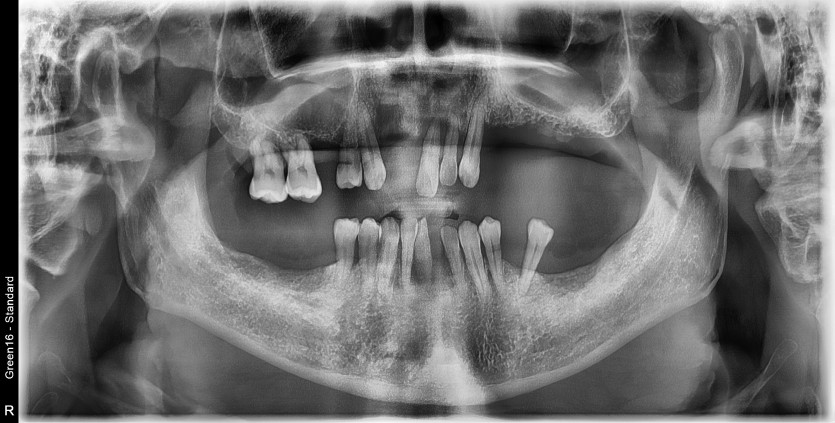

전체 임플란트 증례입니다.

18개의 임플란트로 완성하였습니다.